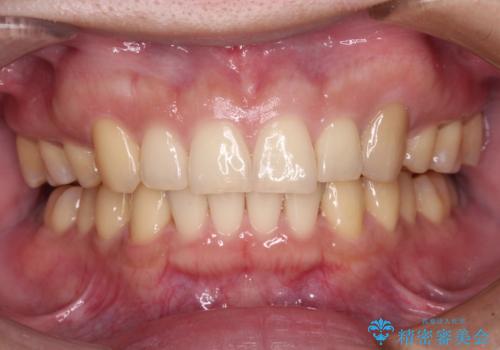

上顎のみの抜歯矯正をインビザラインで行う場合、奥歯の前方移動がインビザラインでは苦手のため、奥歯の咬み合わせが不十分となることがあります。

今回の治療では終了時に奥歯は接触しているものの、接触の程度は物足りないものがある状態でした。今後保定期間に少しずつ奥歯の咬合を改善させていくことになります。